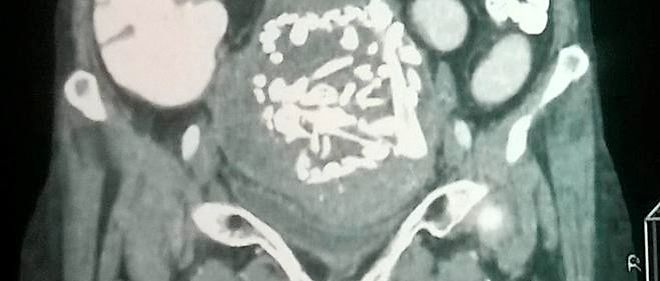

« Ce sont des êtres humains. J’ai des liens avec ces enfants », a déclaré au New York Post cette mère de quatre enfants, dont des triplés. Dans une lettre au père biologique rendue publique, elle écrivait : « Le médecin a transféré trois embryons sains. Il y avait de grandes chances qu’ils se développent… Si vous saviez que vous vouliez seulement deux enfants, pourquoi transférer trois embryons ? » La requête pour un avortement sélectif « a été faite pour sa protection et pour éviter des complications majeures », a affirmé l’avocat du père au Daily Beast. « Dans un sens, en refusant l’avortement, elle risque la vie des trois enfants et peut-être la sienne. » Une très grosse majorité des triplés naissent prématurément.

Brittanyrose Torres, 26 ans, a accepté de devenir mère porteuse pour un couple dont elle a lu l’histoire émouvante sur Facebook. On lui a implanté plusieurs embryons et elle porte aujourd’hui deux garçons et une fille. Le couple lui a demandé d’avorter de l’un des foetus pour réduire les complications médicales et le risque de malformation. Brittanyrose Torres, elle aussi, a refusé. Les parents biologiques « savaient depuis le début que je ne voudrais pas d’avortement, sauf dans le cas d’une question de vie ou de mort », a-t-elle dit dans une interview. Elle aurait signé un contrat qui lui donnerait 25 000 dollars pour un bébé, plus une prime de 5 000 dollars par bébé supplémentaire. Elle a proposé au couple d’en adopter un.